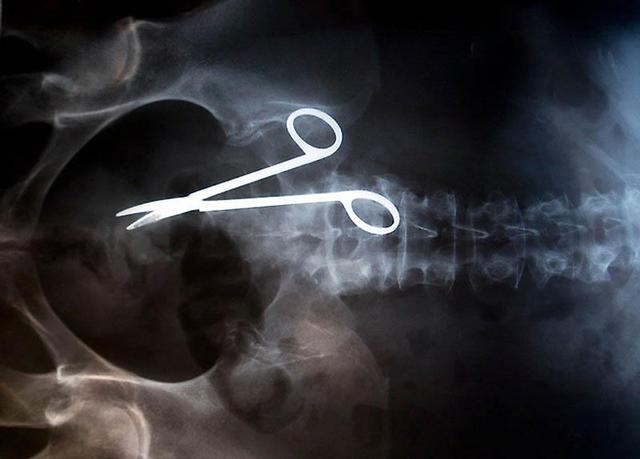

Хирургические ножницы, случайно забытые в теле пациентки после операции. Ножницы были обнаружены лишь через 18 месяцев после операции, т.к. женщина жаловалась на постоянную боль в кишечнике.